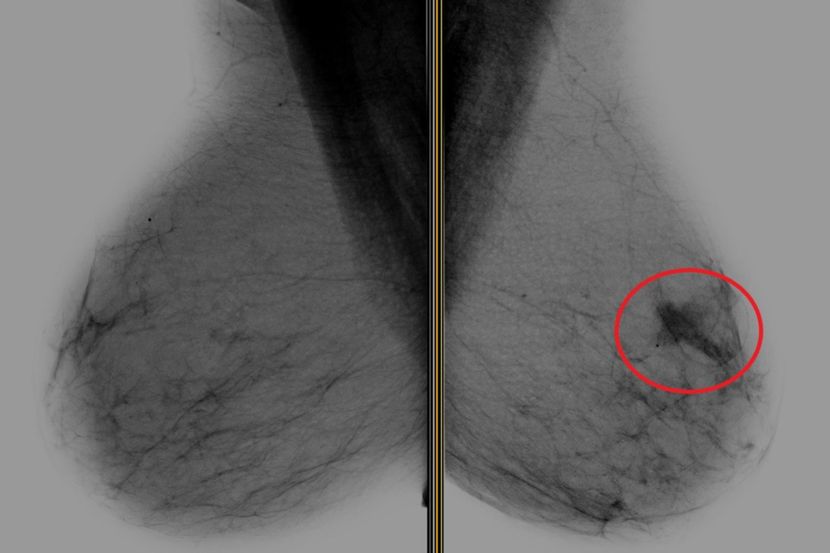

Ova dva snimka magnetnom rezonancom (MRI) napravljena su u razmaku od 10 meseci. Sa leve strane, plava strelica pokazuje na ivicu tumora dojke, a crvena strelica locira snimak biopsije, koji se pojavljuje kao crna tačka. MRI sa desne strane, koji uključuje snimak biopsije, pokazuje da je tumor nestao nakon jedne, ciljane doze zračenja i antihormonske terapije Foto: UT Southwestern Medical Center